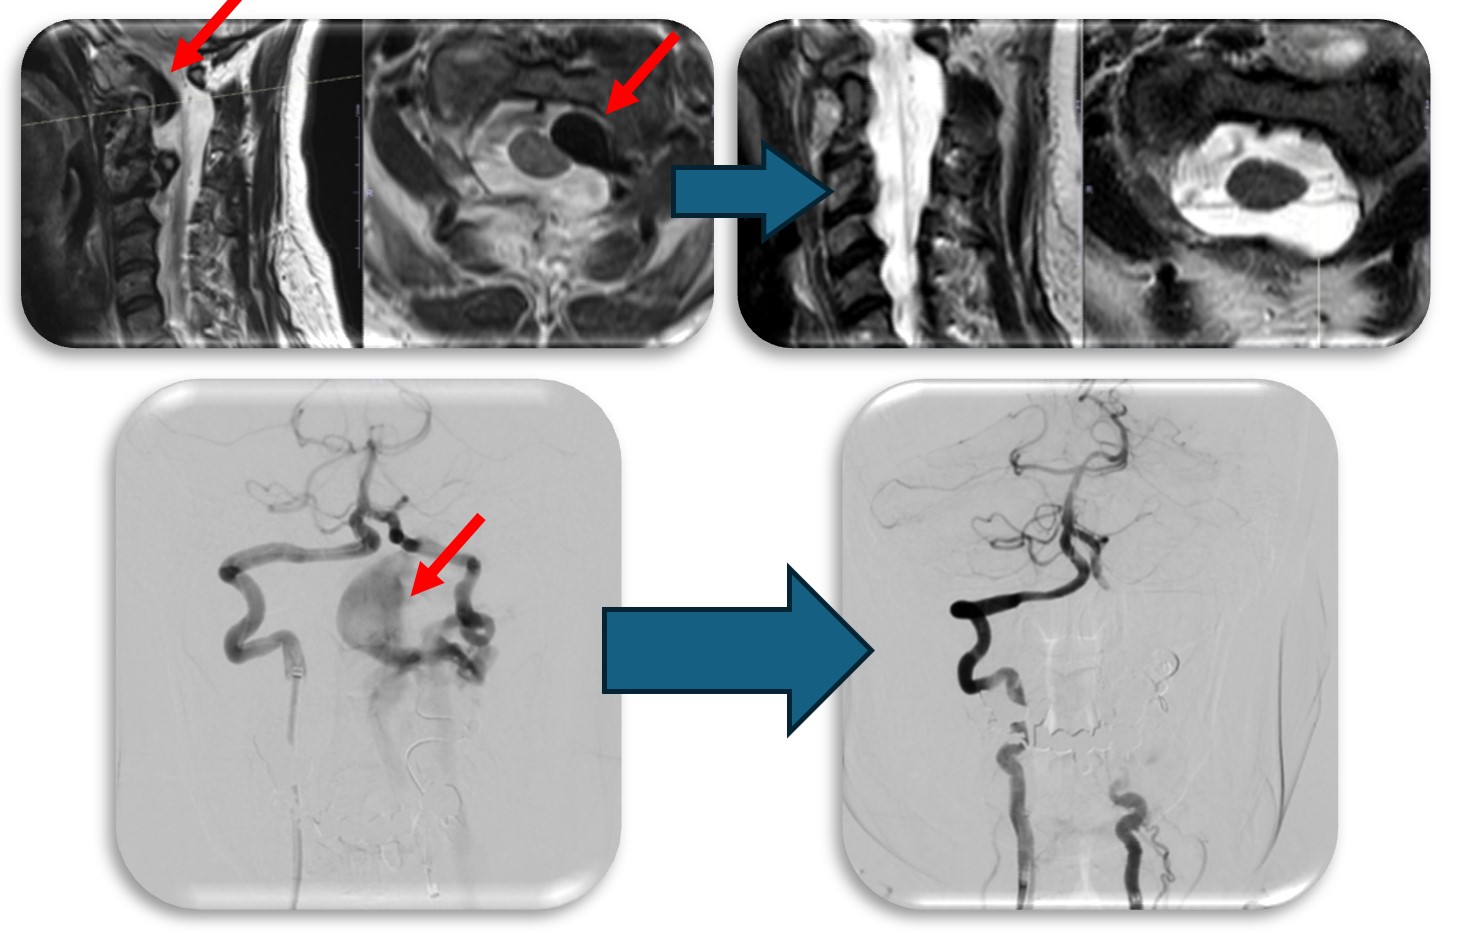

頚部にできた血管奇形の症例です。当初脊髄腫瘍という話で紹介された症例でしたが、巨大な血管奇形でした(赤矢印)。椎骨動脈と脊柱管内の静脈に異常なシャントが原因で巨大な静脈瘤を呈し、それが脊髄を圧迫し神経症状を来していました。この症例はもともと神経繊維腫症1型という遺伝子疾患の既往があったのですが、まれに頚椎や頚椎周囲の血管に奇形を呈することがあります。このような症例は外科的治療は危険性が非常に高く、血管内治療で治療しました。なお、この症例は環軸椎亜脱臼も呈しており今後時期を診て脊椎手術も行う予定です。